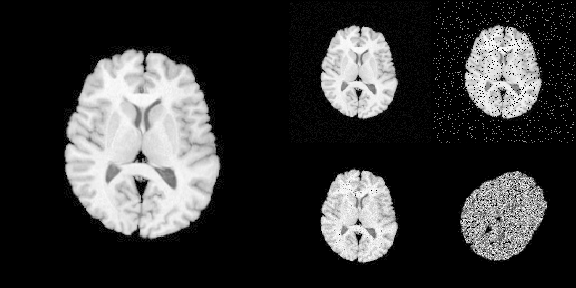

The following R code translates Python code into R:

# >>> img = ants.image_read(ants.get_ants_data('r16'))

img <- ants$image_read(ants$get_ants_data('r16'))

# >>> noise_image1 = ants.add_noise_to_image(img, 'additivegaussian', (0.0, 1.0))

noise_image1 <- ants$add_noise_to_image(

img, 'additivegaussian',

noise_parameters = tuple(0.0, 1.0)

)

# >>> noise_image2 = ants.add_noise_to_image(img, 'saltandpepper', (0.1, 0.0, 100.0))

noise_image2 <- ants$add_noise_to_image(

img, 'saltandpepper',

noise_parameters = tuple(0.1, 0.0, 100.0)

# >>> noise_image3 = ants.add_noise_to_image(img, 'shot', 1.0)

noise_image3 <- ants$add_noise_to_image(

img, 'shot',

noise_parameters = 1.0

# >>> noise_image4 = ants.add_noise_to_image(img, 'speckle', 1.0)

noise_image4 <- ants$add_noise_to_image(

img, 'speckle',

# >>> trans = ants.create_ants_transform(

# >>>   dimension=2, matrix=[[0.707, 0.707], [-.707, 0.707]],

# >>>   translation=[-53, 128])

trans <- as_ANTsTransform(matrix(

c(0.707, 0.707, -53,

-0.707, 0.707, 128),

nrow = 2, byrow = TRUE

), dimension = 2)

# >>> noise_image4 = trans.apply_to_image(noise_image4)

noise_image4 <- trans$apply_to_image(noise_image4)

To load imaging data into R

# Use [] to convert ANTsImage into R array

is.array(img[])

#> [1] TRUE

# plot via R

layout(matrix(c(1,1,2,3,1,1,4,5), nrow = 2, byrow = TRUE))

par(mar = c(0.1, 0.1, 0.1, 0.1), bg = "black", fg = "white")

pal <- grDevices::gray.colors(256, start = 0, end = 1)

image(img[], asp = 1, axes = FALSE,

col = pal, zlim = c(0, 255), ylim = c(1, 0))

image(noise_image1[], asp = 1, axes = FALSE,

image(noise_image2[], asp = 1, axes = FALSE,

image(noise_image3[], asp = 1, axes = FALSE,

image(noise_image4[], asp = 1, axes = FALSE,